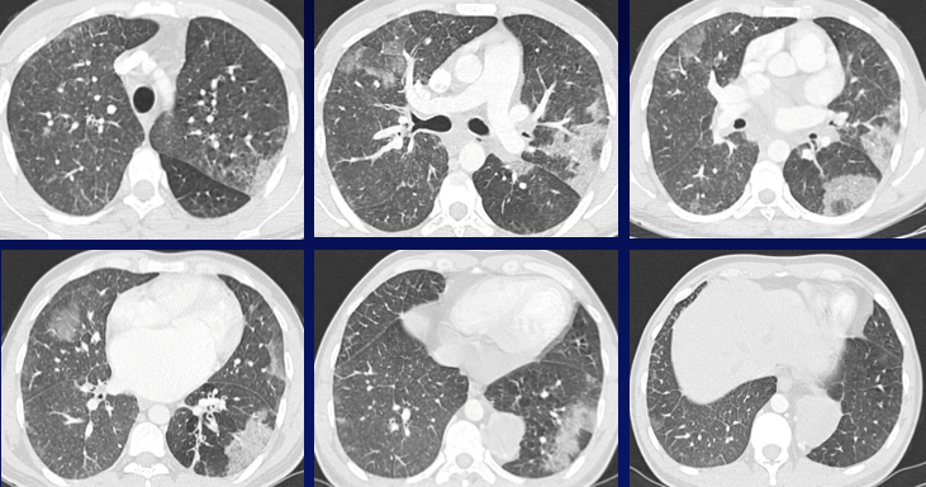

Jeune homme de 27 ans

Hémoptysies de faible abondance

Récidivantes depuis 3 mois avec dyspnée d’effort

Anémie hypochrome microcytaire à 6g/dl

QUEL EST VOTRE DIAGNOSTIC ?

A – Lymphome médiastinal postérieur avec atteinte pulmonaire

B – Maladie de Castelman avec hémorragie alvéolaire

C – Tumeur neurogène avec hémorragie alvéolaire

D – Séquestration intra-lobaire avec œdème pulmonaire et rétrécissement mitral

E – Séquestration extra-lobaire avec œdème pulmonaire, hémorragie alvéolaire et rétrécissement mitral